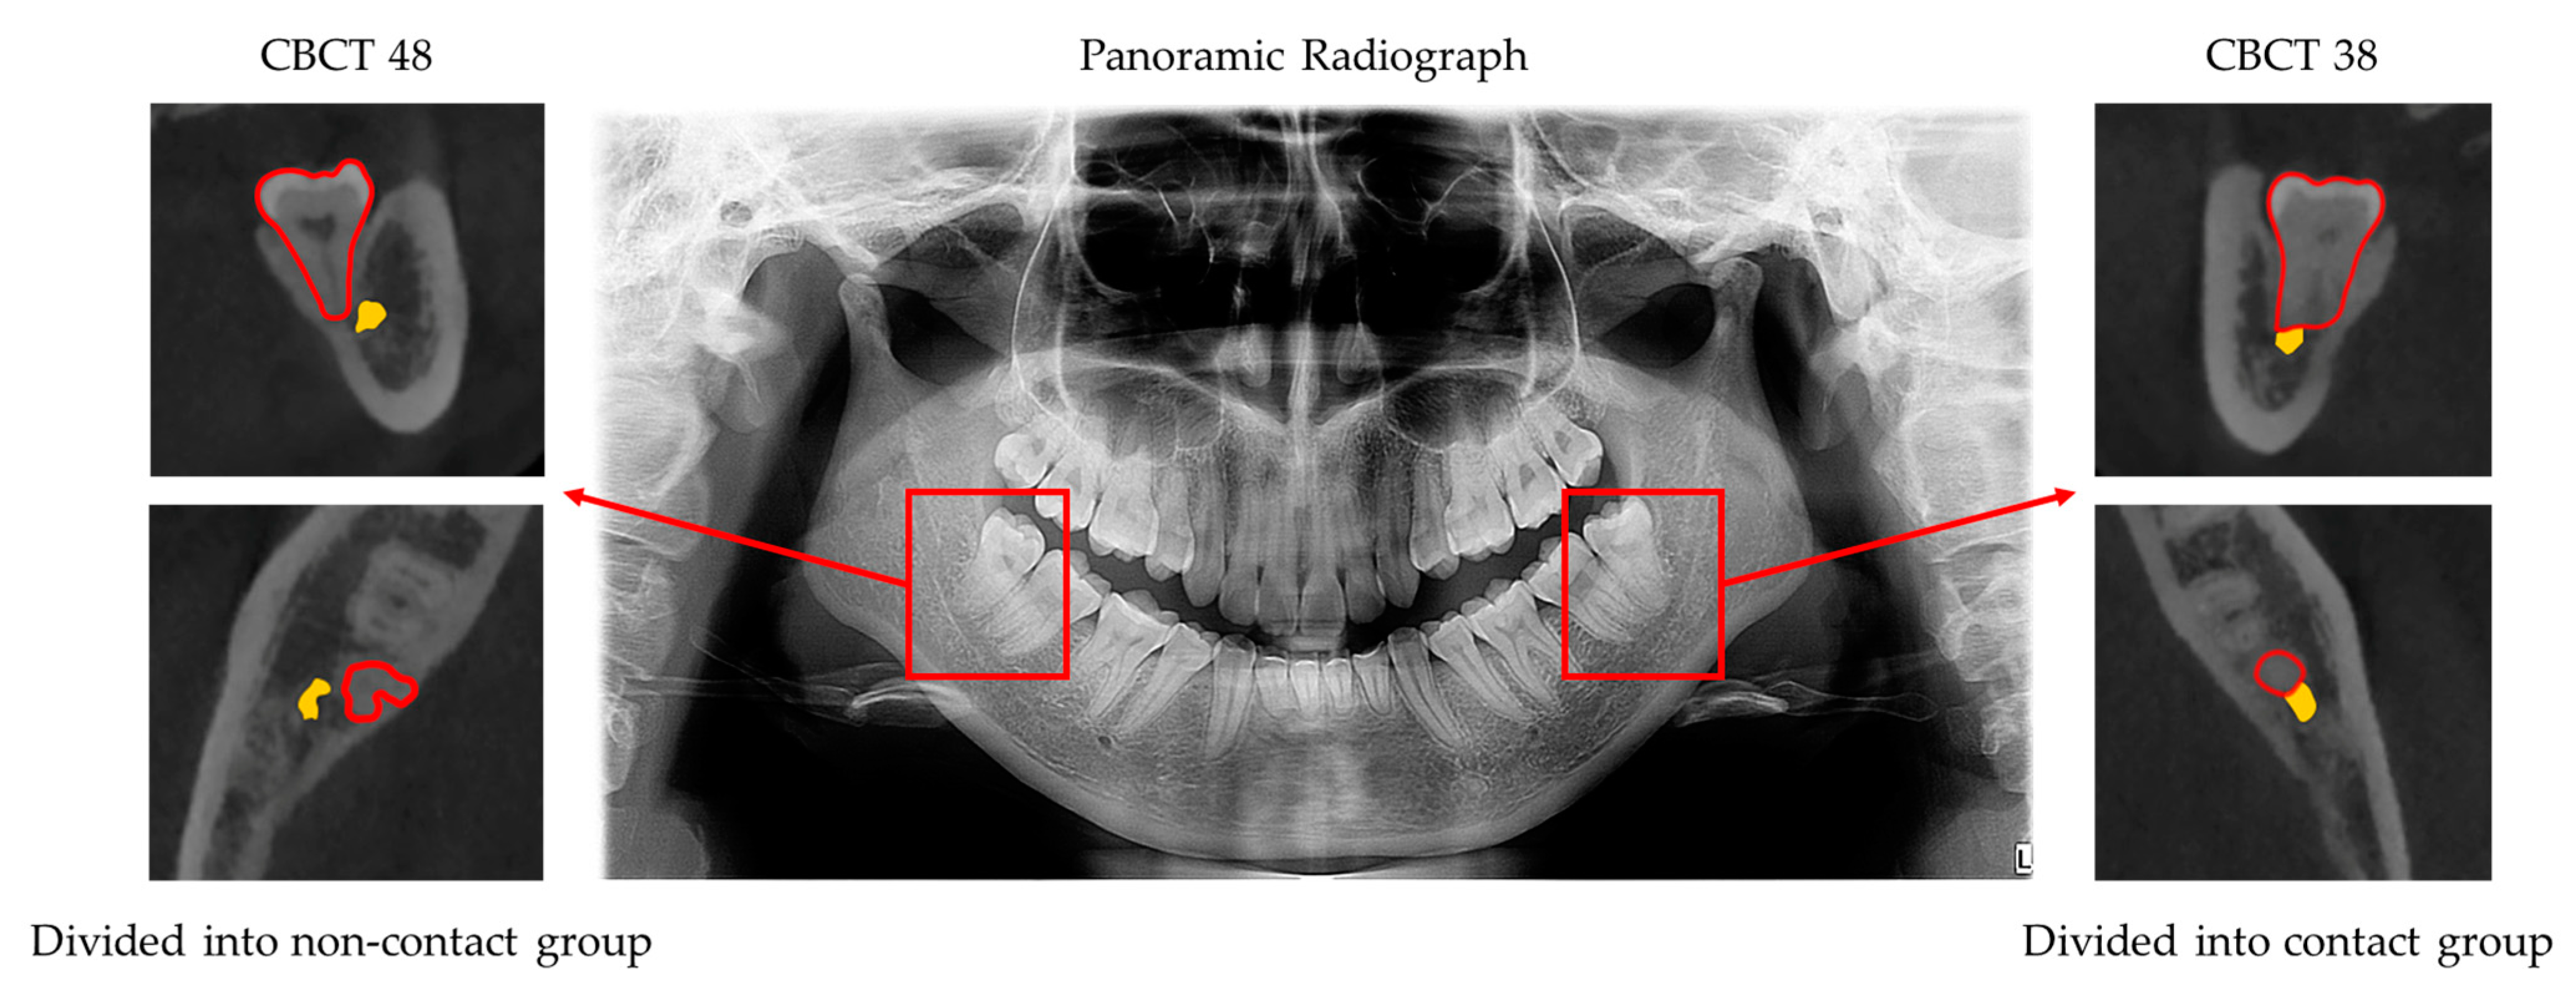

2.1. Image Data Set